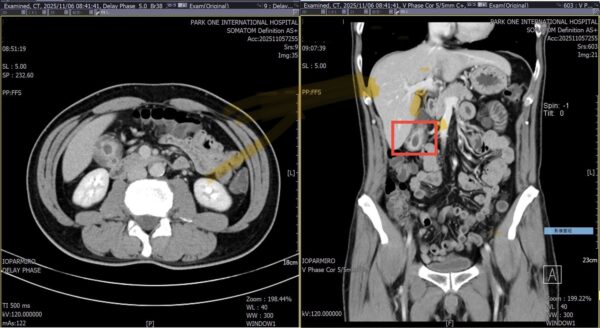

圖2:博田國際醫院電腦斷層掃描發現,男子的膽囊壁竟異常廣泛性增厚達正常的六倍,確認為臨床上常與膽結石混淆的「膽囊腺肌症」。